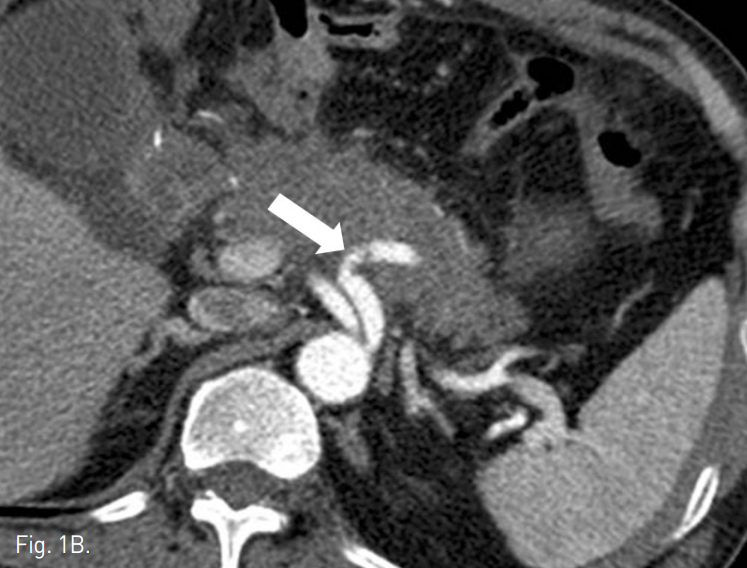

조영증강 복부 CT에서 잔류위의 점막부 조영증강이 일부 끊어져 있는 소견이 보였고, 그 주변으로 혈종과 액체저류 소견이 보여 잔류위 봉합부의 열개(dehiscence)가 있는 것으로 생각된다(Fig. 1a). 액체저류는 주변으로 파급되어 췌장을 둘러싸고 퍼지는 양상이며 비장동맥 주위까지 침윤되어 있었다. 비장동맥의 근위부가 약간 불규칙하게 보였으나 급성 출혈이나 가성동맥류 소견은 뚜렷하지 않았다(Fig. 1b).

Fig. 1

A. Contrast-enhanced CT scan shows focal dehiscence in the residual stomach wall (arrow) with surrounding fluid collection.

B. Proximal splenic artery shows focal luminal irregulari ty (arrow). But there was no evidence of arterial bleding.